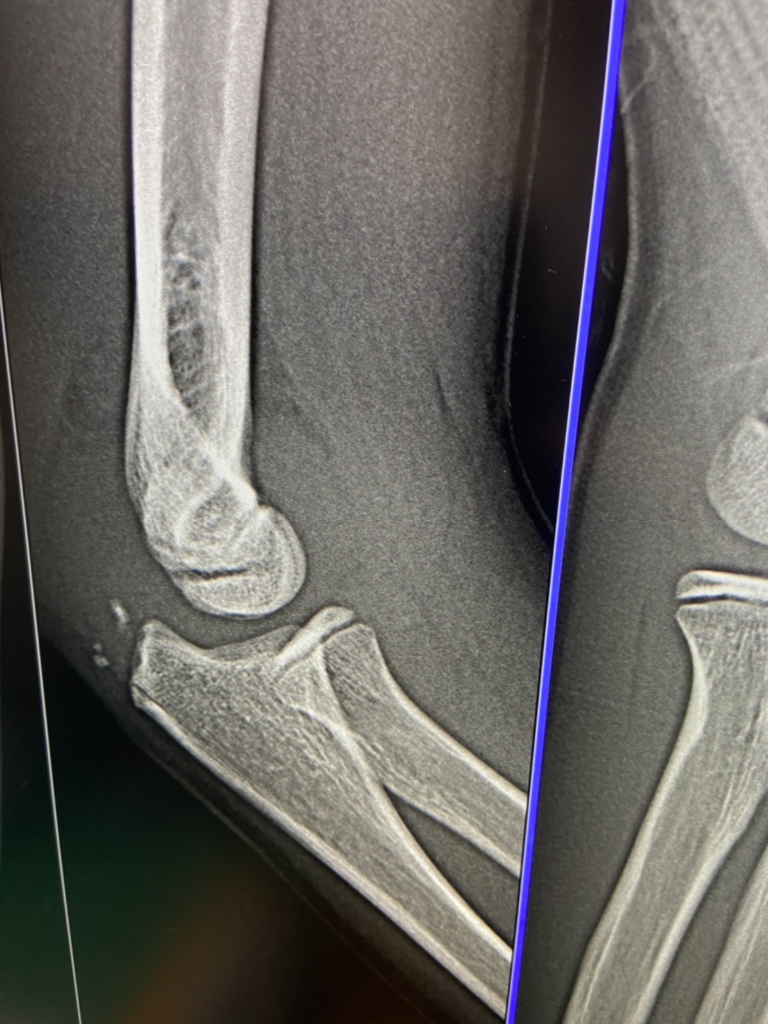

すぐさま近隣の医療機関に搬送し、レントゲン検査読影の結果、

ごらんのとおり右肘頭骨折と確定。

帰阪後完全固定を施し、固定6週間程度、除去後のリハビリ6週間、

完全機能回復まで約3か月を要す、となった。